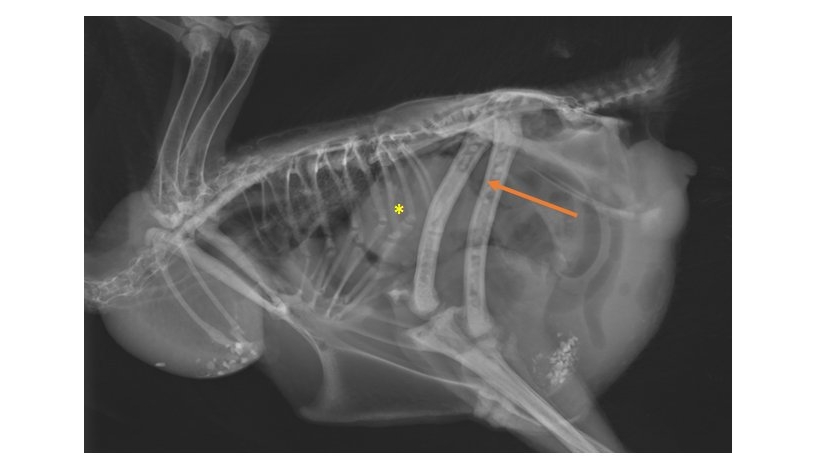

Mercredi 1 Avril 2026 Animaux de compagniePhoto n° 1 : Radiographie de tumeur ovarienne (*) et métastases fémorales (->) en vue latérale droite.

© Service d'imagerie du Chuv-Ac de l'ENVA, 2020